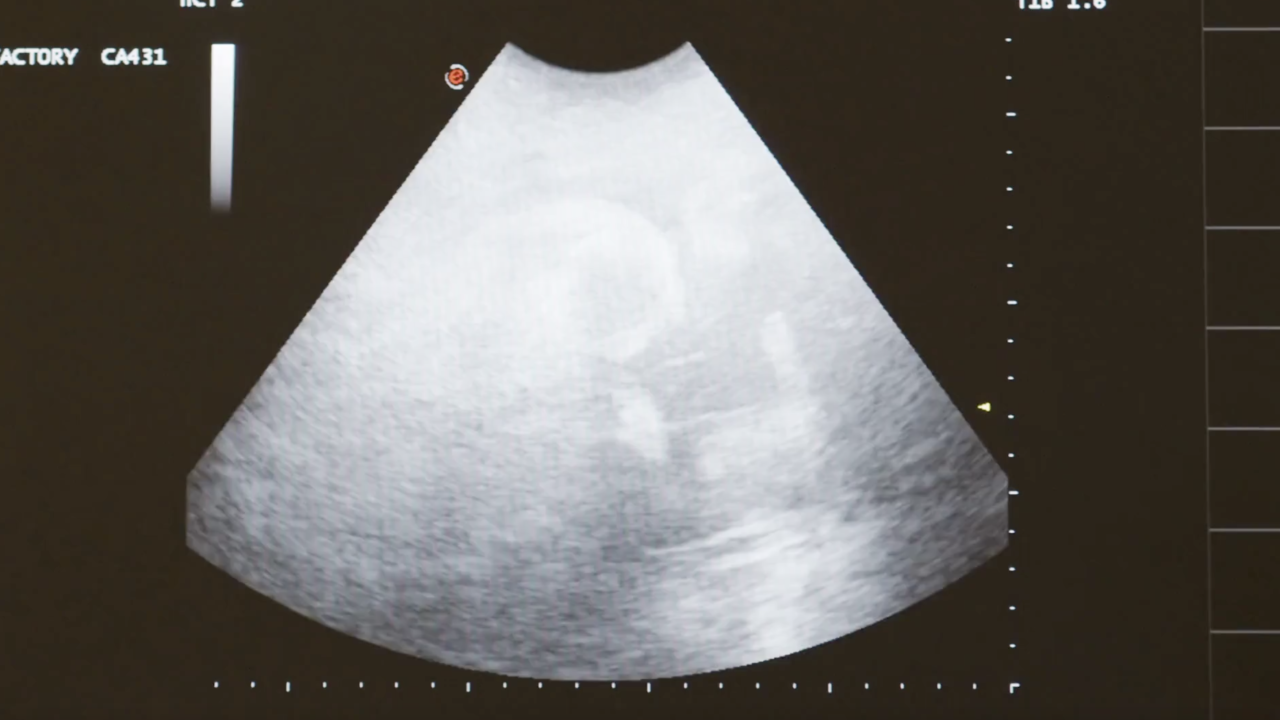

She went to the emergency room and had multiple ultrasounds.

“And that’s when the doctor came back and stated ya know there's no baby anymore," Elek said. “At that moment my heart dropped and that’s when we started having the conversation was COVID the cause of my miscarriage?”